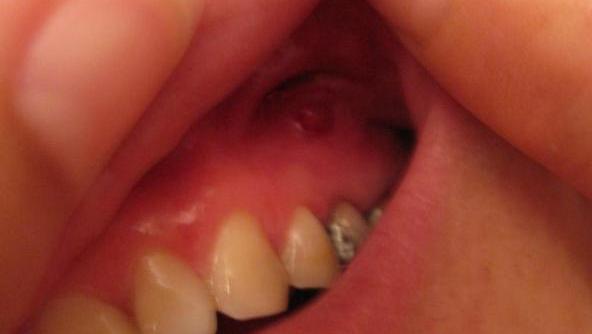

牙龈上的脓包 , 学名“窦道”。

通俗来说就是牙齿有龋齿

或者缺损等病因

导致牙根发炎后根尖周组织化脓,

脓液穿通骨壁和软组织流到牙龈表面,

形成脓包。

一般呈粟米大小的乳头形状。

更有甚者,

脓液会穿通到皮肤表面 形成肉芽肿结节,

影响颜面部美观。